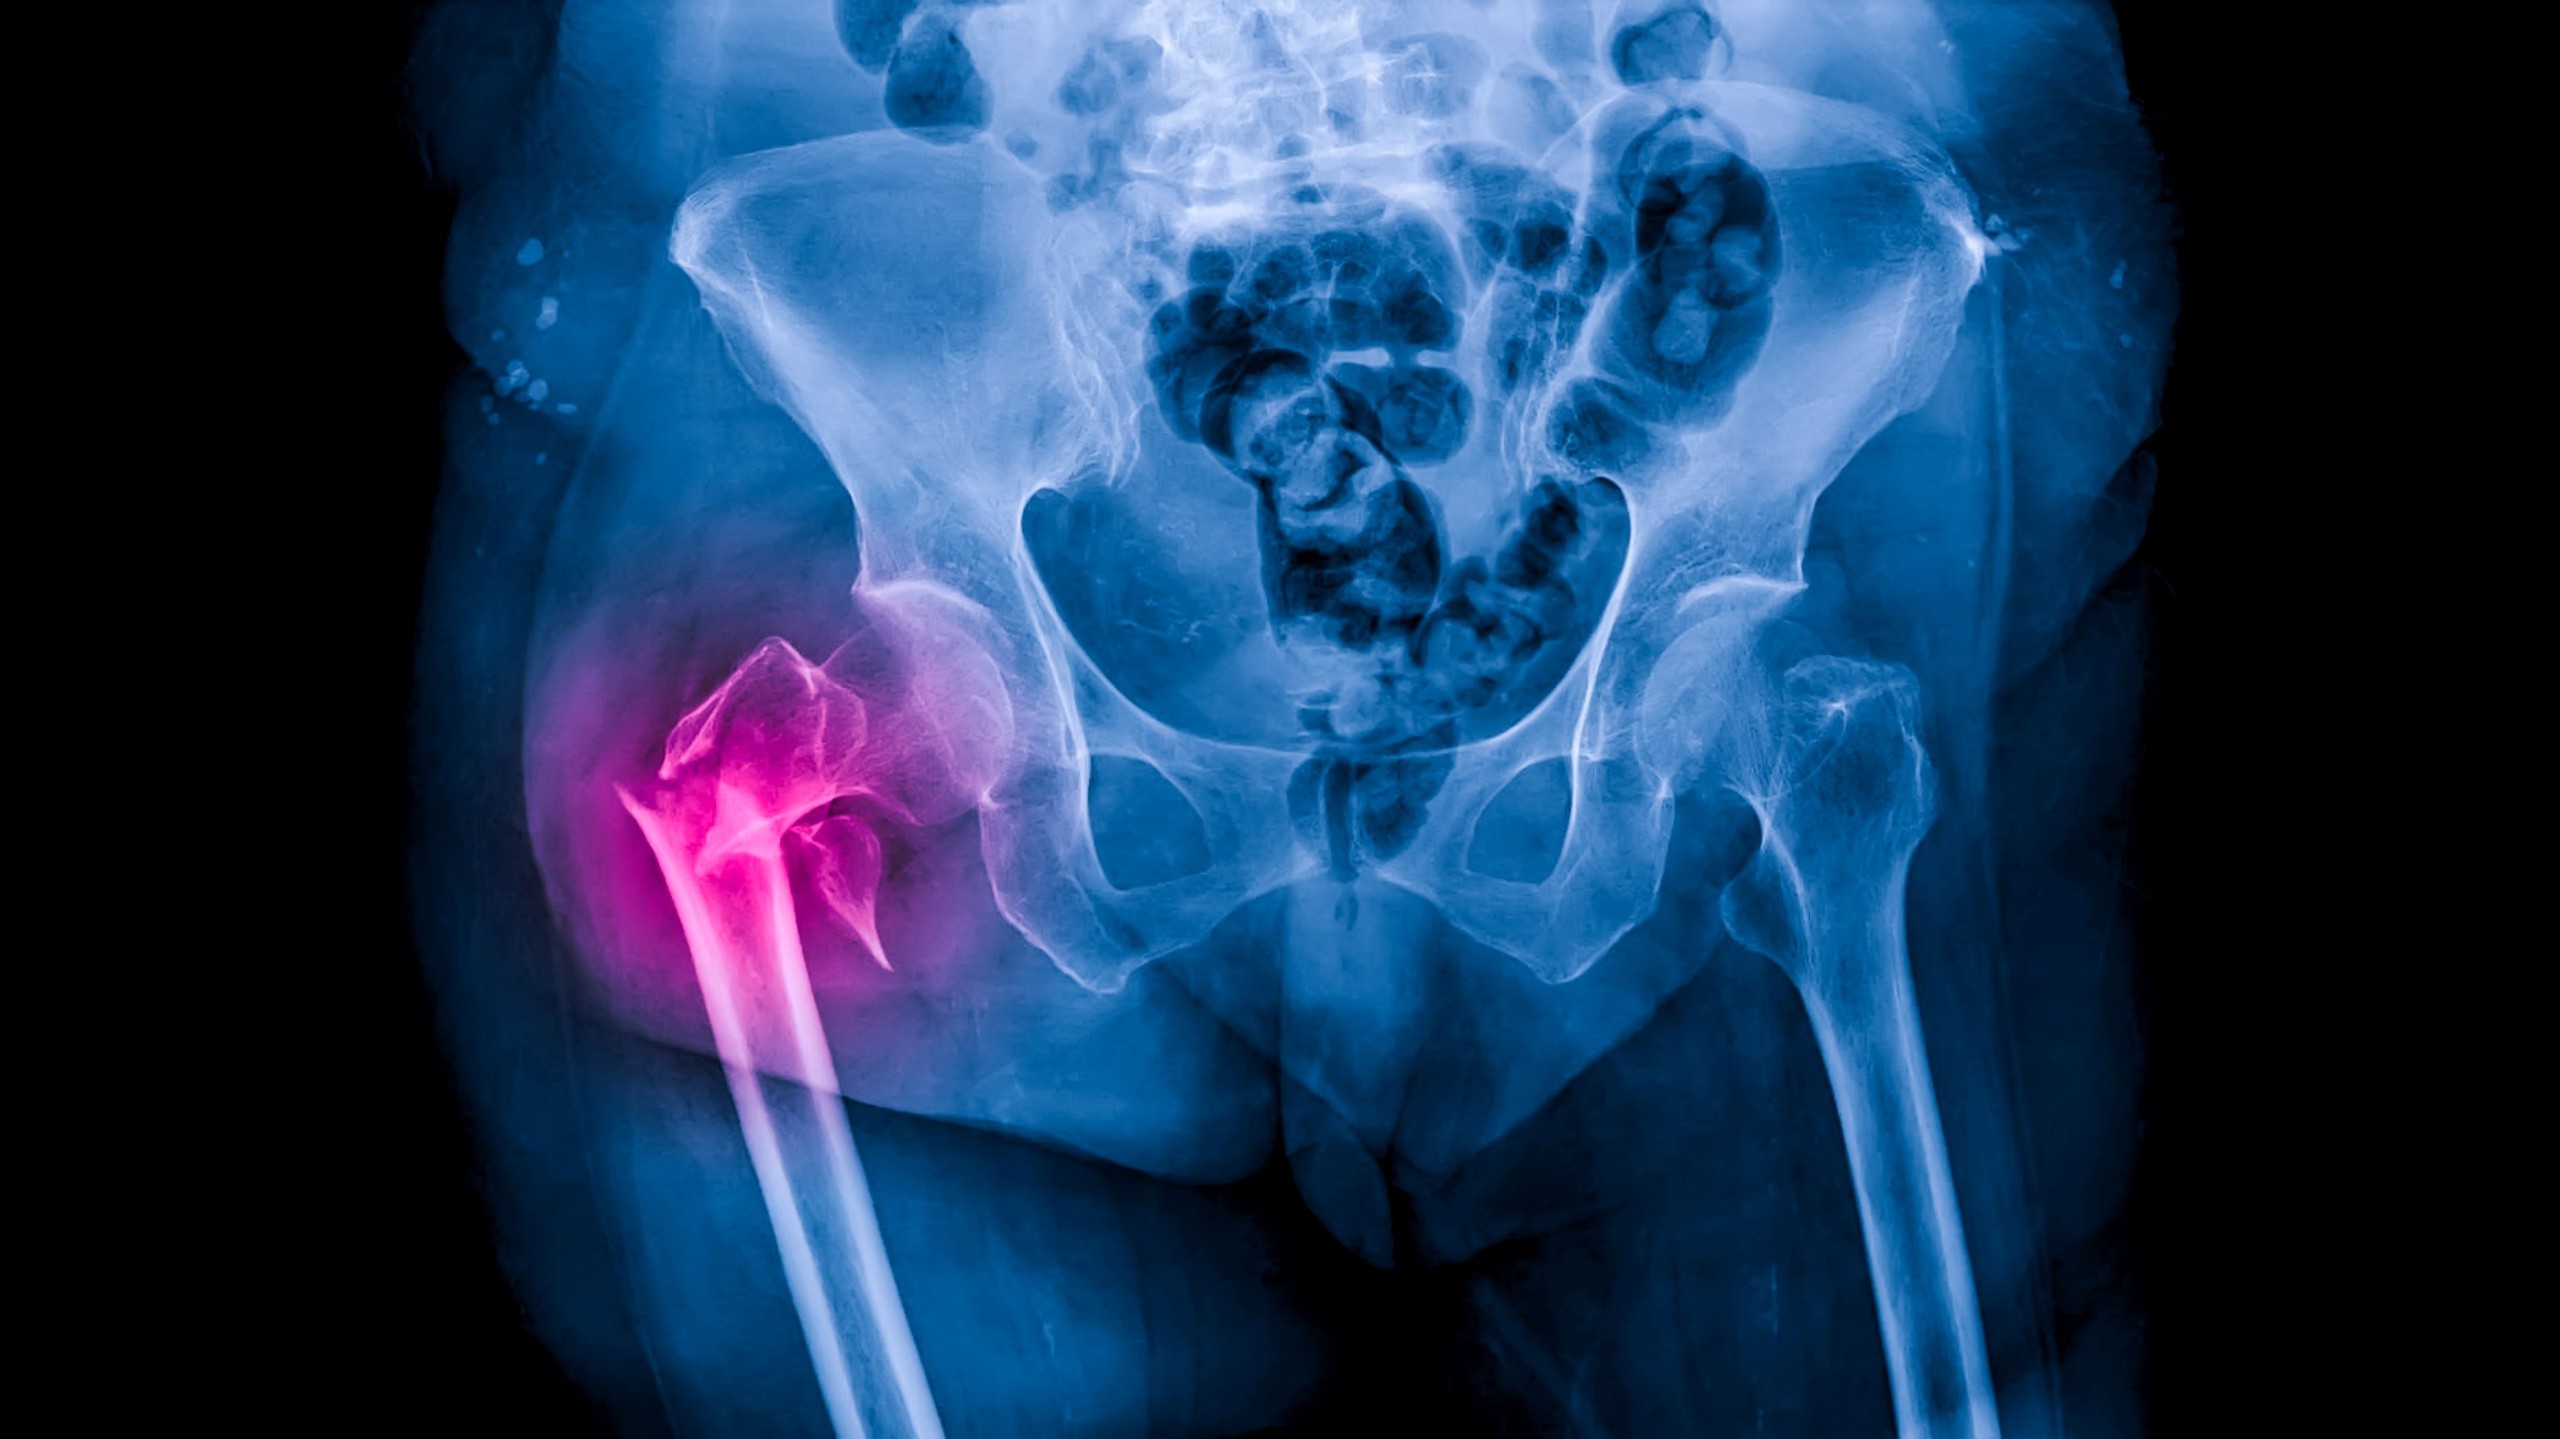

Az osteopenia a csont ásványianyag-tartalmának csökkenését jelenti. Világszerte a felnőttek körülbelül 40 százalékát érinti, különösen gyakori a menopauza után lévő nőknél és az idősebb korosztályban. Önmagában általában nem jár fájdalommal vagy látványos tünetekkel, ezért sokan csak akkor szembesülnek vele, amikor csonttörést szenvednek, vagy valamilyen kockázati tényező miatt csontsűrűség-vizsgálatra küldik őket – írja a ScienceAlert.

Az osteopenia felismerése azért fontos, mert ilyenkor még sokat lehet tenni a folyamat lassításáért. A csontsűrűséget leggyakrabban DEXA-vizsgálattal mérik, amely alacsony sugárterhelésű röntgeneljárás. Az eredményt általában úgynevezett T-score értékben adják meg: a mínusz 1,0 és mínusz 2,5 közötti tartomány osteopeniára utal, míg a mínusz 2,5 alatti érték már csontritkulásnak felel meg. A kezelés és a megelőzés célja elsősorban az, hogy lassítsák a további csontvesztést, és csökkentsék a törések esélyét. Ebben fontos szerepe van a rendszeres mozgásnak. A testsúlyt terhelő mozgásformák, például a gyaloglás, a tánc vagy a kocogás serkenthetik a csontképződést, az erősítő edzések pedig az izmokat és a csontokat is stabilabbá tehetik.